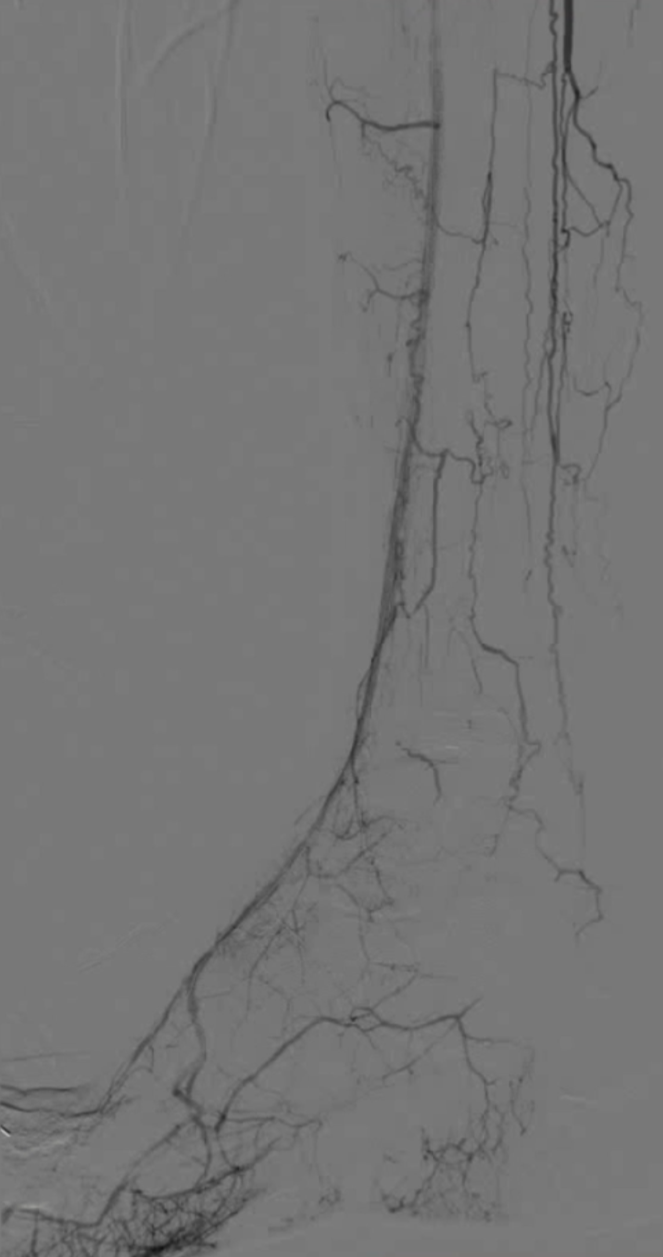

TAO动脉病变模式有 abrupt occlusion(突然闭塞)、Localized stenosis(局限性狭窄)、Moth-eaten stenosis(虫蚀样狭窄)等,还可能出现不规则侧支循环、侧支循环早期形成、树根样侧支、迂曲静脉等情况。

48岁男性,右足溃疡反复发作,多次PTA+DCB治疗

2023.3 右足部溃疡2个月,行PTA

2024.5,再发溃疡4个月,先后两次PTA

2024.9,溃疡未愈合,胫前动脉、胫后动脉PTA+DCB